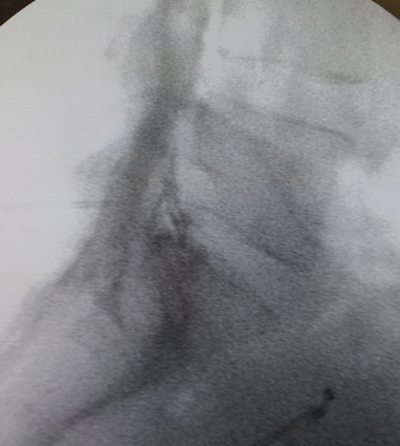

Figura 2